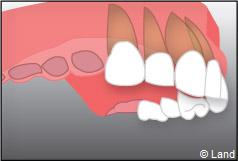

Un implant dentaire est une racine artificielle, placée par le chirurgien-dentiste dans l’os alvéolaire de l’un des maxillaires en remplacement de la racine d’une dent extraite, qui servira de support à une prothèse. Sa forme est généralement cylindrique ou légèrement conique, ressemblant à une vis, en titane ou en zircone, avec une connexion au niveau supérieur, à l’emplacement de la gencive, pour permettre la pose d’un élément prothétique par vissage ou scellement. Son diamètre varie entre 3 et 5 mm et sa longueur entre 8 et 15 mm. La pose d’un implant, réalisée sous anesthésie locale, est totalement indolore. Elle se pratique au cabinet dentaire ou en clinique.

– le remplacement d’une dent unitaire. Grâce à ce procédé, il n’y a pas de mutilation des dents voisines.